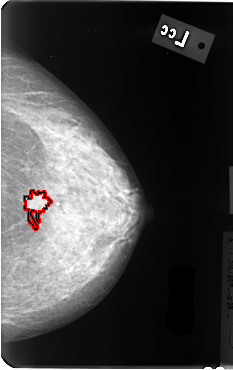

B_3085_1.LEFT_CC

LEFT_CC LINES 4808 PIXELS_PER_LINE 3024 BITS_PER_PIXEL 12 RESOLUTION 50 OVERLAY

FILE: B_3085_1.LEFT_CC.OVERLAY

TOTAL_ABNORMALITIES 1

ABNORMALITY 1

LESION_TYPE MASS SHAPE IRREGULAR-ARCHITECTURAL_DISTORTION MARGINS SPICULATED

ASSESSMENT 4

SUBTLETY 4

PATHOLOGY MALIGNANT

TOTAL_OUTLINES 1

BOUNDARY